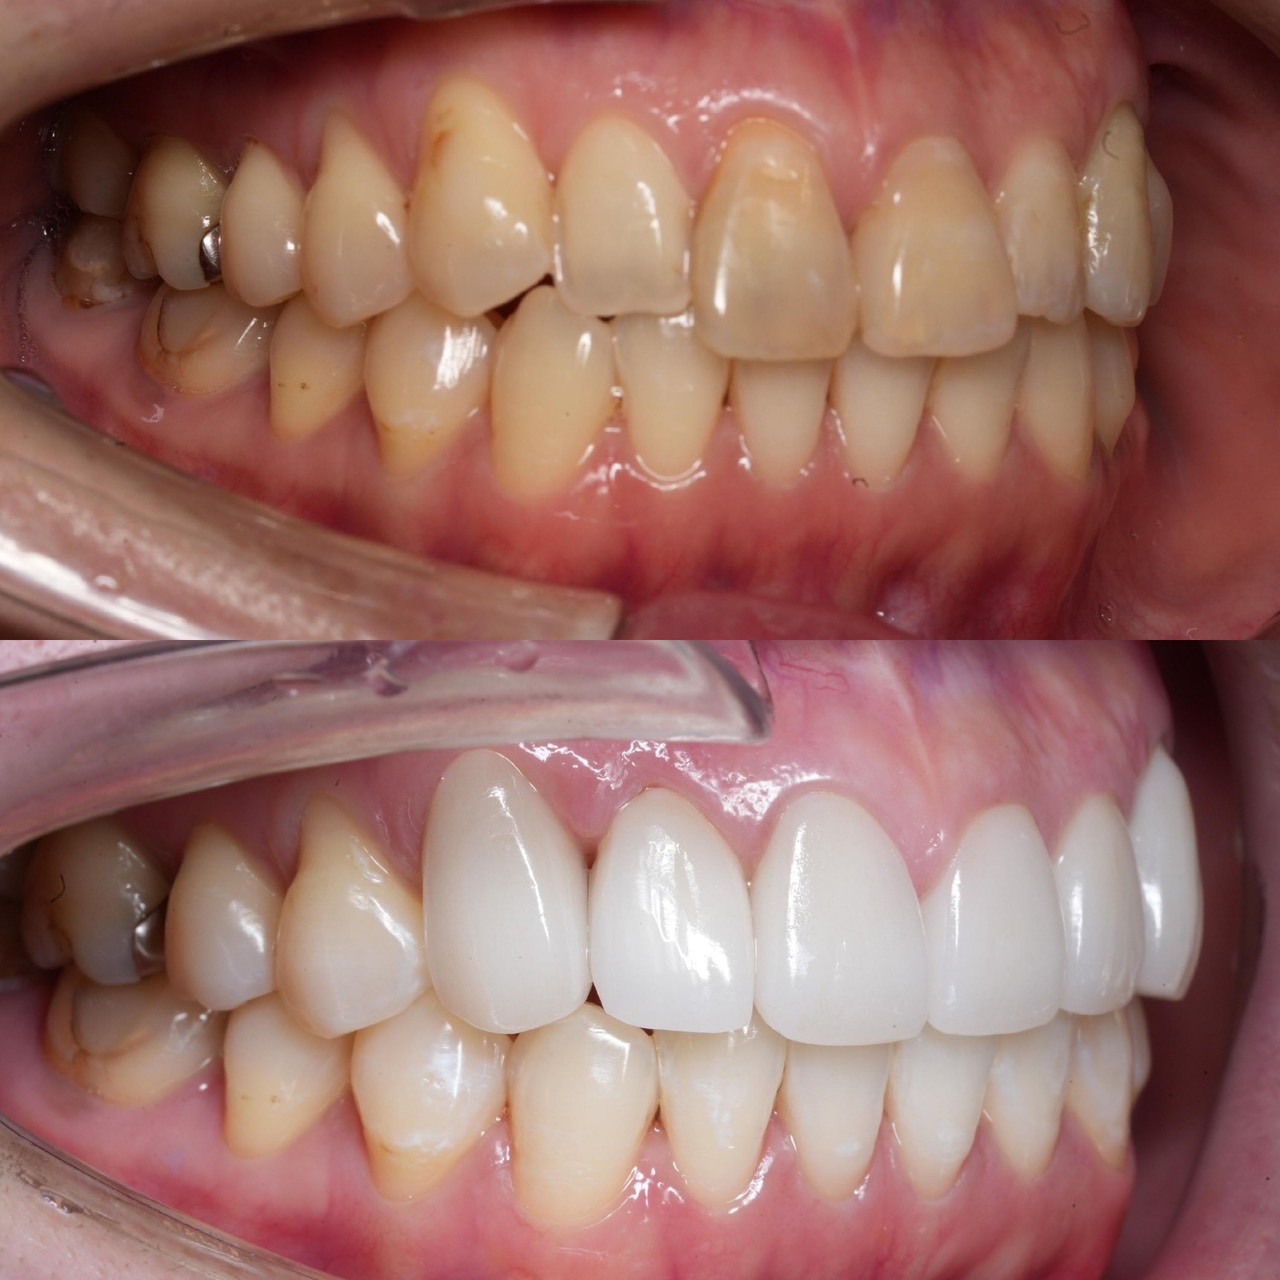

Case026

他院ですでに3本セラミック治療を行っている男性の患者様です。

歯並びと色を変えたいということで当院にお越しくださいました。

・透明感のあるセラミックに変更

・前に出ている歯を内側に入れてスマートな印象に

したことにより、とても洗練された口元になったと思います。

この白い色もとてもお似合いの方で、治した私もセット後に思わず「似合いますね」と言ってしまいました。

この方の場合は

・既に歯を3本削られている

・前医で入れた大きなセラミックは矯正しても小さくはならない

・色を変えたい

以上の理由でセラミック矯正を選んでおります。